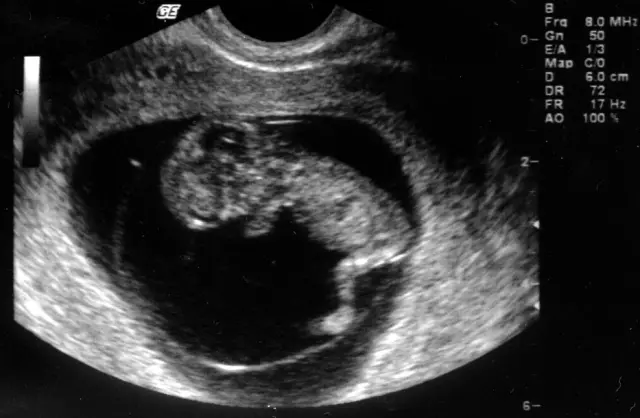

V naši ambulanti se vedno trudimo imeti čimbolj strokoven pristop. To lahko dosežemo le z nenehnim izobraževanjem in spremljanjem razvoja medicinskih postopkov doma ter v tujini. Tako smo se med drugim specializirali za različne preglede, kot je nuhalna svetlina Ptuj.